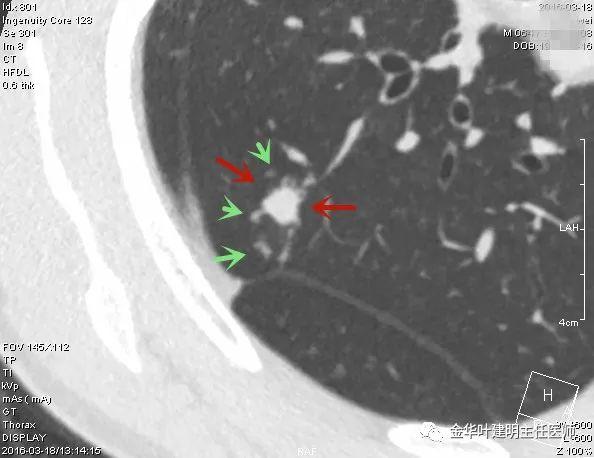

叶建明谈结节:检查发现肺实性结节怎么办?个人版实用指南

上图是肺内淋巴结。但我们看有明显血管进入病灶,胸膜似有牵拉,恶性的特征也不少。